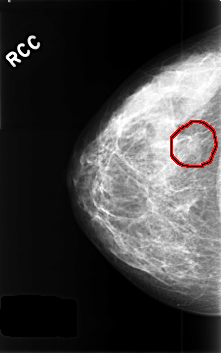

C_0437_1.RIGHT_CC

FILE: C_0437_1.RIGHT_CC.OVERLAY

TOTAL_ABNORMALITIES 1

ABNORMALITY 1

LESION_TYPE MASS SHAPE FOCAL_ASYMMETRIC_DENSITY MARGINS N/A

ASSESSMENT 3

SUBTLETY 3

PATHOLOGY BENIGN_WITHOUT_CALLBACK

TOTAL_OUTLINES 1

BOUNDARY